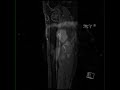

Enchondroma Tibia

32-year-old female presenting for chronic left knee pain. The images demonstrate a T1 isointense, proton density isointense, STIR hyperintense mass centered within the medullary cavity of the proximal left tibia. There is involvement of the epiphysis and metaphysis. The lesion heterogeneously enhances. There are components of the lesion which are STIR hypointense demonstrating a ring and arc configuration. The imaging findings are most compatible with a benign chondroid lesion such as an enchondroma. Enchondroma is a type of benign medullary cartilaginous neoplasm usually found in children or young adults. Peak incidence is around 10-30 years of age. The lesions arise from rests of growth plate cartilage that subsequently proliferate and slowly enlarge.